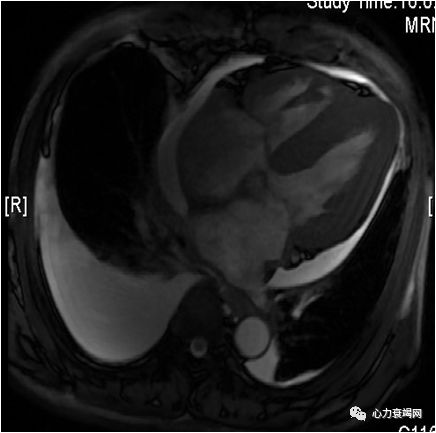

➤ 心脏MRI增强:心肌首过灌注可见心内膜下灌注减低,延迟扫描左、右心室可见弥漫性强化,以心内膜下强化为著。

➤ 心肌淀粉样变性,左室收缩及舒张运动减弱;少量心包积液;右侧中量胸腔积液,左侧少量胸腔积液。